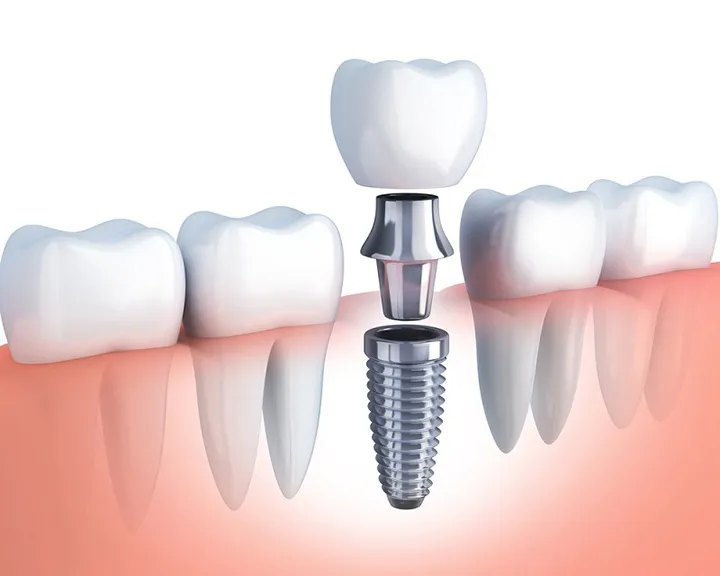

Một trong những phương pháp thay thế răng đã mất an toàn, hiệu quả đó là trồng răng Implant. Cụ thể, phần chân răng giả sẽ được gắn chặt với xương hàm. Mục đích chính là thay thế chiếc răng đã mất, giúp bạn ăn uống dễ dàng hơn. Nhìn chung, răng Implant trông khá giống răng thật. Nhờ vậy bạn sẽ cảm thấy tự tin hơn mỗi khi nở nụ cười hoặc giao tiếp với bạn bè xung quanh.

Răng Implant được cấu tạo bởi 3 phần chính, cụ thể là trụ Implant, khớp nối Abutment, mão răng sứ. Phần trụ Implant thường được làm từ titanium và được gắn vào xương hàm một cách chắc chắn. Mão răng sứ được gắn vào trụ Implant và được cố định bằng khớp nối Abutment. Nhiệm vụ chính của khớp nối là giữ cho răng không trượt hoặc lung lay.